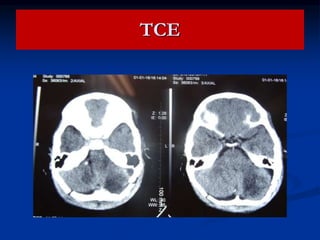

TCE

HEMATOMA EPIDURAL

Ocurre en el 1 % de los TCE

Es ocasionado por ruptura de arteria

meningea media, pero en 15 % es

ocasionado por ruptura de senos

venosos.

75 % es asociado fractura de craneo. La

dura es separada del craneo por sangre

y se incrementa hasta que el vaso es

comprimido por el coagulo.

Son localizados sobre la convexidad en la fosa

craneal media,pero puede haber en la fosa

anterior.

Pueden ocurrir en la fosa posterior.

Ocurre en personas jovenes. Hay perdida de la

conciencia, despues un periodo lucido para

despues caer en coma. Hemiplejia, pupila

ipsilateral o no; CEFALEA Y ALTERACION

CONCIENCIA

Puede haber signos cerebelosos, rigidez de nuca,

Por TAC es la forma de lente BICONVEXO.

Herniacion, y muerte puede ser rapido, por lo que

requiere CIRUGIA URGENTE